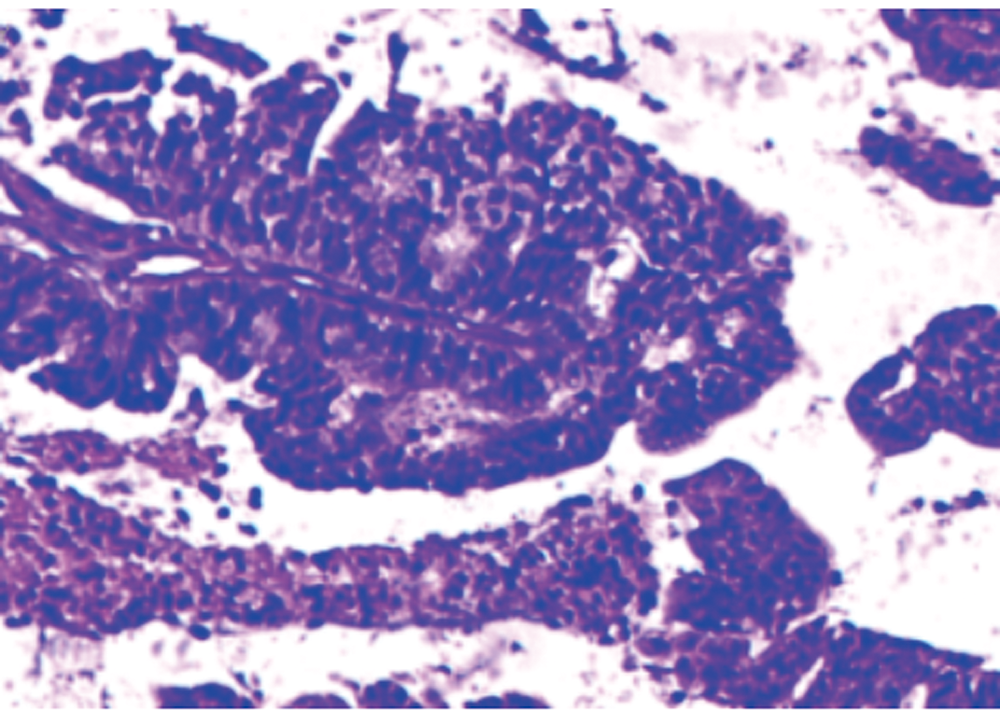

盐酸安罗替尼为多靶点小分子酪氨酸激酶抑制剂,可作用于肿瘤新生血管,并诱导肿瘤细胞凋亡,其广泛应用于肾细胞癌、结直肠癌、肝癌等肿瘤的治疗。本例应用放化疗联合盐酸安罗替尼治疗复发性子宫内膜癌患者,取得满意的疗效。